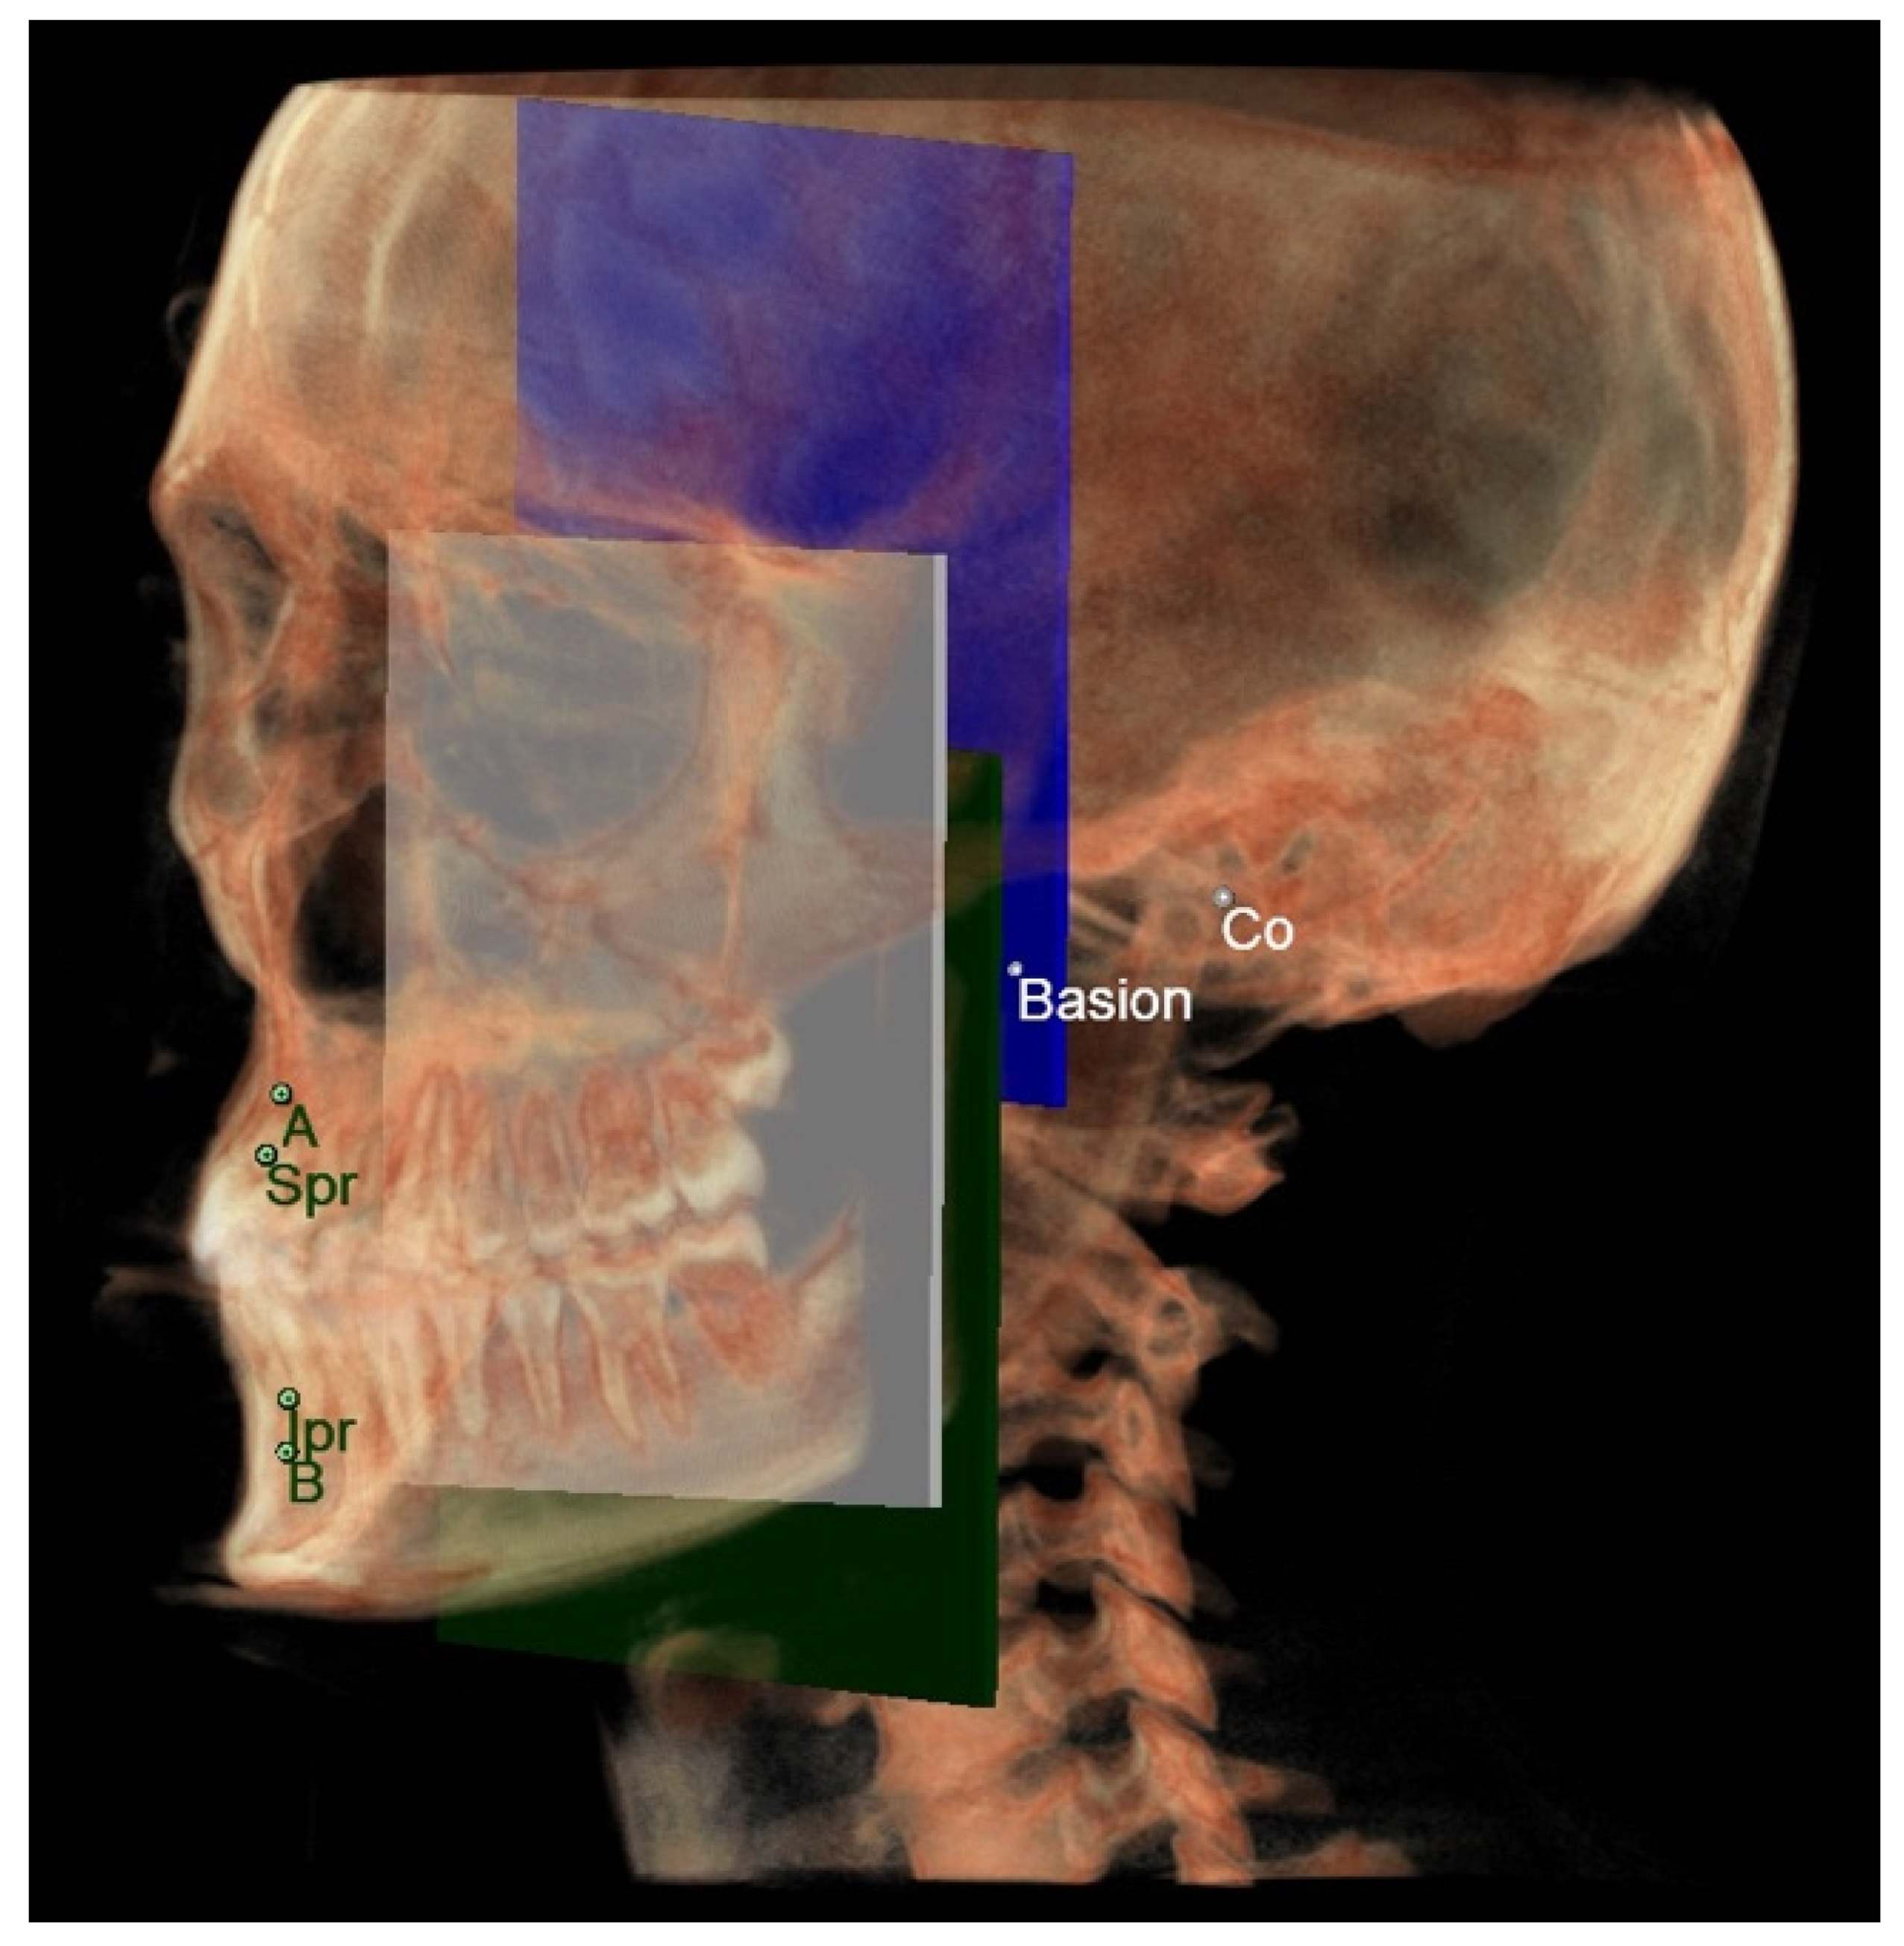

- The maxillary skeletal arch (Figure 6) was measured from point A to a plane passing through the PNS and parallel to the coronal plane.

- The mandibular skeletal arch (Figure 7) was measured from the point B to a plane passing through the two lingual tuberosity and normal to the axial plane

- The maxillary dento-alveolar arch (Figure 8) was measured from the point SPr to a plane passing through the PNS and parallel to the coronal plane.

- The mandibular dento-alveolar arch (Figure 9) was measured from the point IPr to a plane passing through the two lingual tuberosity and normal to the axial plane.

- The middle cranial floor (Figure 10) was determined by the distance from Ba to a plane passing through the two anterior clinoid processes and normal to the axial plane. The anterior clinoid processes were chosen as they represented the most posterior point of the anterior cranial floor and the most anterior point of the middle cranial floor.

- The mandibular ramus was measured from the right and left condylion to a plane passing through the right and left lingual tuberosity and normal to the axial plane (Figure 10).